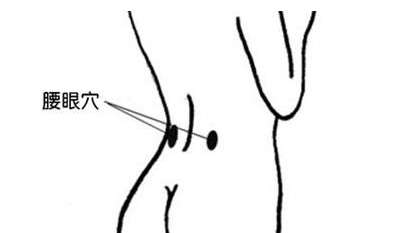

- 腰眼穴

- 腰眼穴为外奇穴,在腰部,第4腰椎棘突下,旁开约3.5寸的凹陷中.

- 腰眼:第四腰椎棘突下旁开3至4寸